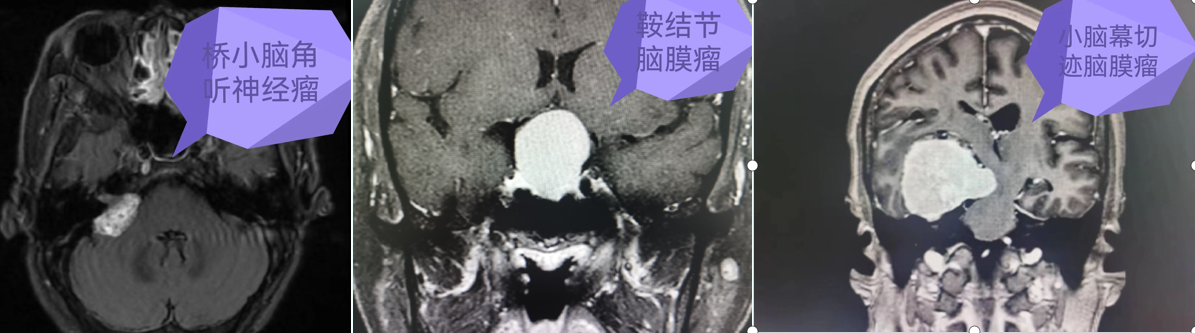

图片 7.png

挑战生命禁区,颅底、侧颅底占位微创切除术

从Ommaya囊侧脑室置入术到大脑半球、小脑半球占位切除术,从垂体瘤到颅底、侧颅底等复杂颅内占位切除术,凭借先进的微创技术与高精尖的设备,为众多患者解除了病痛,让患者重新找回了生活的精彩。

目前,肿瘤医院能熟练开展神经导航引导下、显微镜及神经内镜微创手术治疗各种神经肿瘤(脑膜瘤、胶质瘤、垂体瘤、听神经瘤、脑转移瘤、脑室系统肿瘤等);微型机器人引导下深部及重要功能区脑组织病变活检术;脑血管病(高血压脑出血、血管畸形、动脉瘤、烟雾病)及颅脑损伤手术;各种类型脑积水的分流手术;面肌痉挛、三叉神经痛、痉挛型脑瘫、帕金森、脑梗死的诊治;脑脓肿、椎管内感染等各种复杂的颅内感染性疾病的综合治疗;去骨瓣减压术后钛网或PEEK材料颅骨修补术;频发型癫痫的迷走神经刺激术(VNS);癌痛、昏迷促醒治疗等。